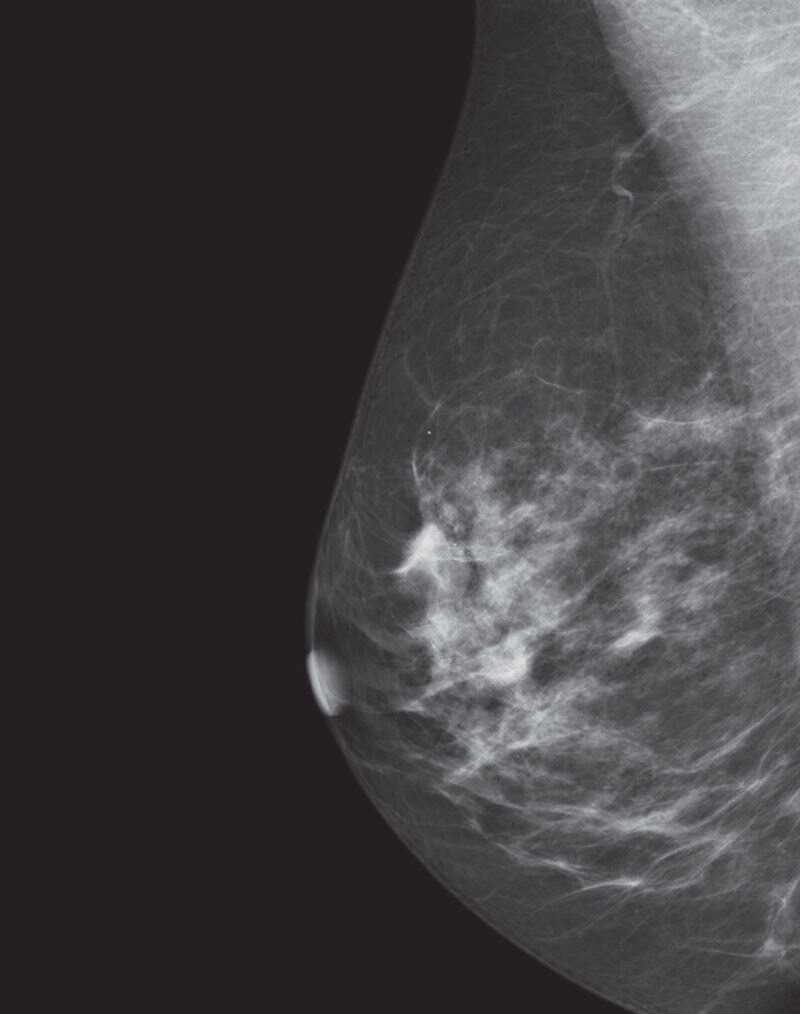

Deep learning in 3D breast image reconstruction

Pristina Recon DL

Pristina Recon DL* pushes 3D mammography past limits, delivering images with greater purity. A paradigm shift born from GE HealthCare’s pioneering AIR™ Recon DL, it operates a dual DL technology that reveals fine details, minimizing artifacts and perceived noise1,2